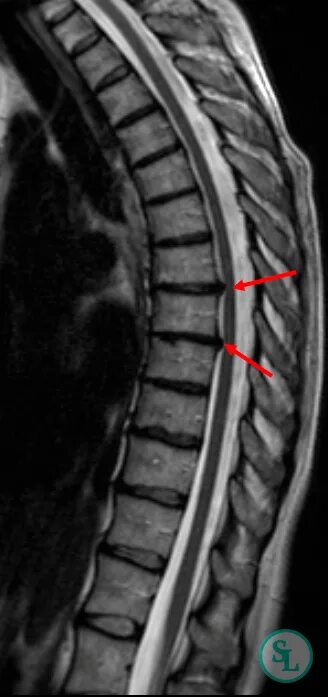

Как выглядит грыжа позвоночника на мрт